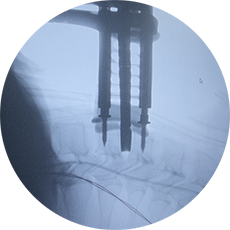

In cazul Elenei, realizarea interventiei prin abord minim-invaziv a insemnat un progres semnificativ. Echipa de neurochirurgi din spitalul nostru a efectuat o artrodeza intersomatica cu Cage tip PLIF (Posterior Lumbar Interbody Fusion) cu osteosinteza posterioara cu suruburi si tija. Intreaga procedura a fost sigura pentru pacienta si a permis disparitia durerilor invalidante si o recuperare rapida, cu externare in a treia zi post-operator.

Aparatul de radiologie intra-operatorie este de mare ajutor intrucat permite efectuarea unor interventii ophisticate sub control radioscopic in timp real. De exemplu, in fracturile vertebrale prin compresie tratate prin vertebroplastie, introducerea cu precizie a cimentului in corpul vertebral tasat se face sub control radiologic in timpul operatiei.